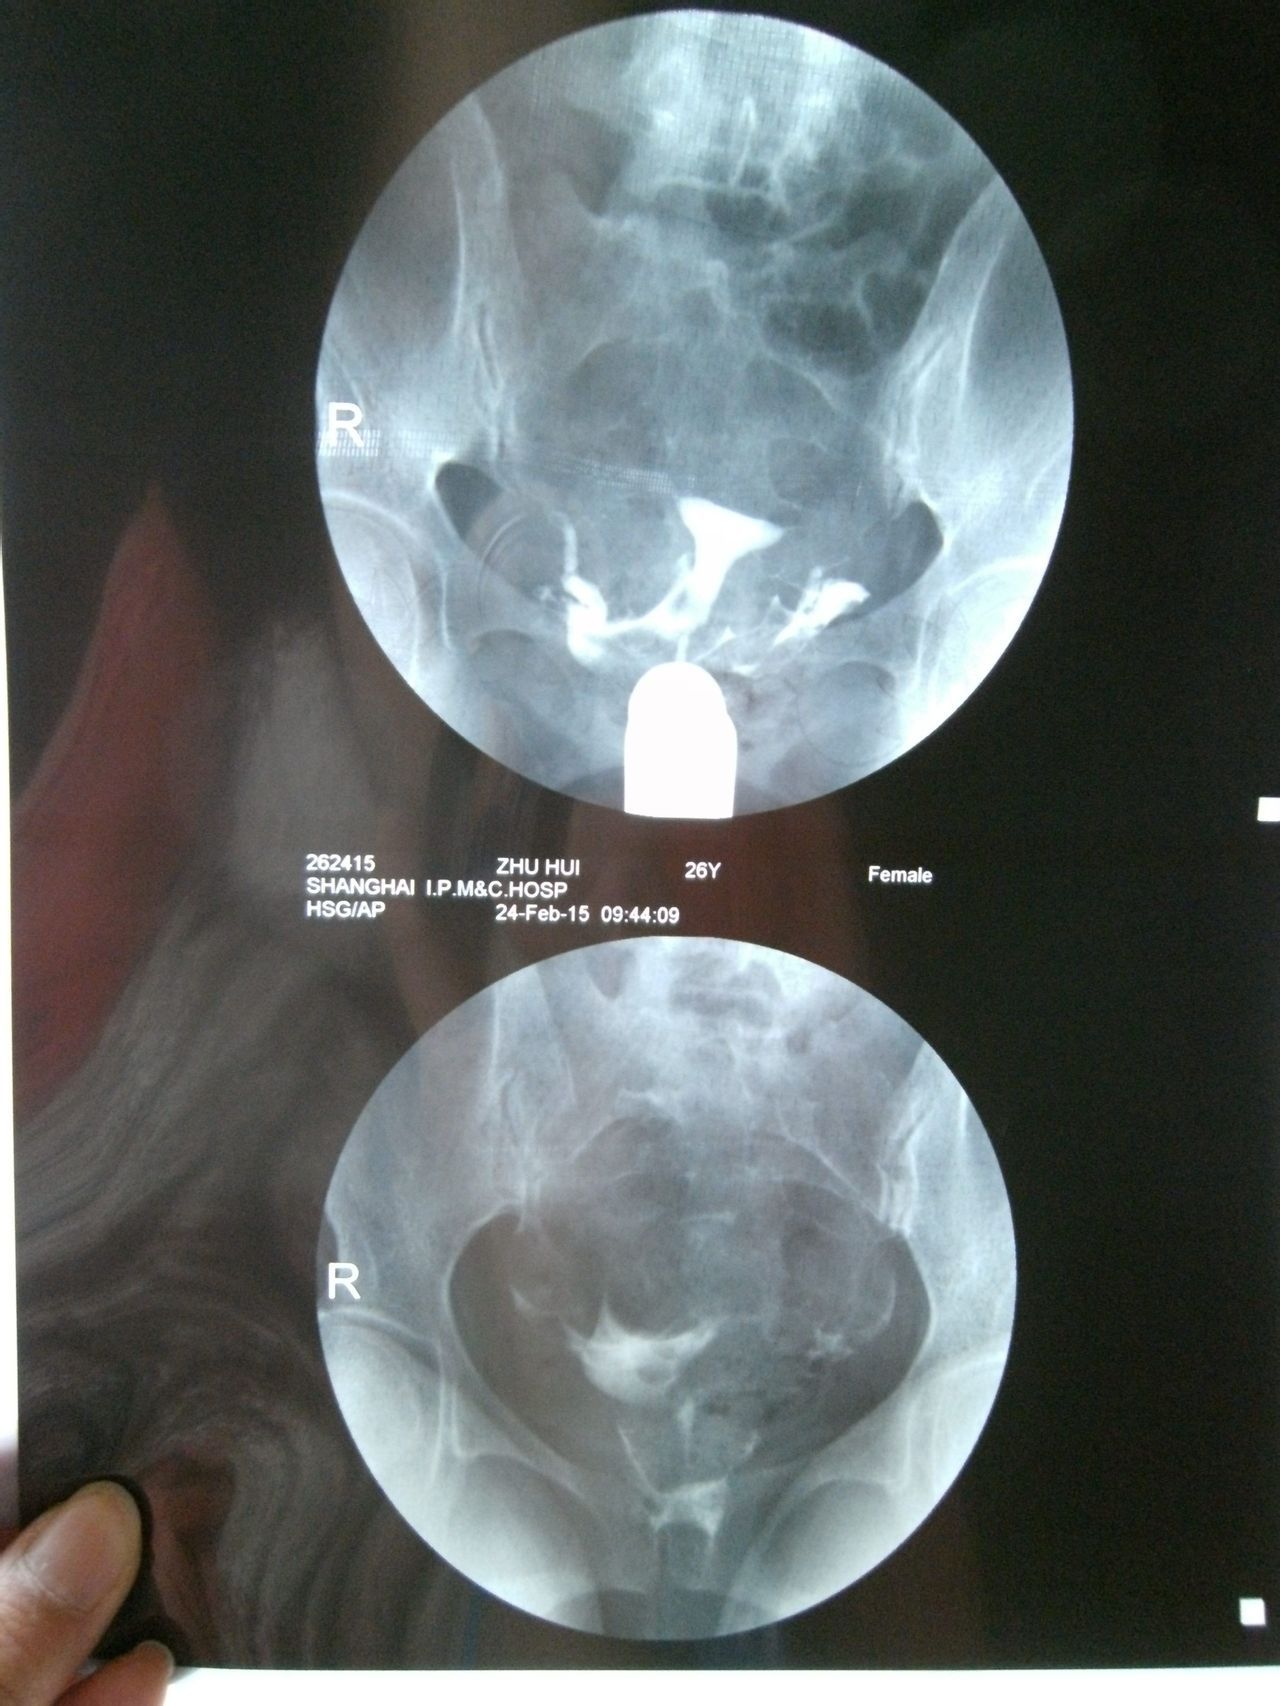

双侧输卵管通而不畅选择哪种治疗方案,谢谢 1、结婚1年多没有做避孕措施;2、我88年,我老公87年,老公检查没什么问题;我做常规检查都正常,在当地三甲医院做过B超(见上传图片),做过6项雌激素(见上传照片);3、量基础体温有排卵,但是拿大卫测试纸却不显示排卵。做过一段时间中药还是没怀孕,现在不知道下一步怎么办?求得解决,谢谢…… 造影报告写着:放射学表现:盆腔平片:盆腔内未见异常密度影。注入造影剂后即刻盆腔摄片:宫腔大小形态正常,腔壁光整。双侧输卵管显影,形态柔软。20分钟后复查摄片:盆腔内见造影剂均匀涂抹,双侧输卵管内少量造影剂残留。放射学诊断:子宫腔正常,双侧输卵管通而不畅。 点击展开 匿名用户 2015-03-06 21:29 为您推荐: 其他回答 你好,联系下次月经过后3-7天内可以去做个输卵管通液,一般是有效果的 天使7737 2015-03-06 23:07 相关问题 您好,我现在双侧输卵管通而不畅,我想治疗,有什么方法吗? 双侧输卵管通而不畅有哪些治疗方案 有没有懂中医的人,帮我看看这个方子和这个治疗方案,谢谢 我是通过造影查出双侧输卵管通而不畅

1、结婚1年多没有做避孕措施;2、我88年,我老公87年,老公检查没什么问题;我做常规检查都正常,在当地三甲医院做过B超(见上传图片),做过6项雌激素(见上传照片);3、量基础体温有排卵,但是拿大卫测试纸却不显示排卵。做过一段时间中药还是没怀孕,现在不知道下一步怎么办?求得解决,谢谢…… 造影报告写着:放射学表现:盆腔平片:盆腔内未见异常密度影。注入造影剂后即刻盆腔摄片:宫腔大小形态正常,腔壁光整。双侧输卵管显影,形态柔软。20分钟后复查摄片:盆腔内见造影剂均匀涂抹,双侧输卵管内少量造影剂残留。放射学诊断:子宫腔正常,双侧输卵管通而不畅。